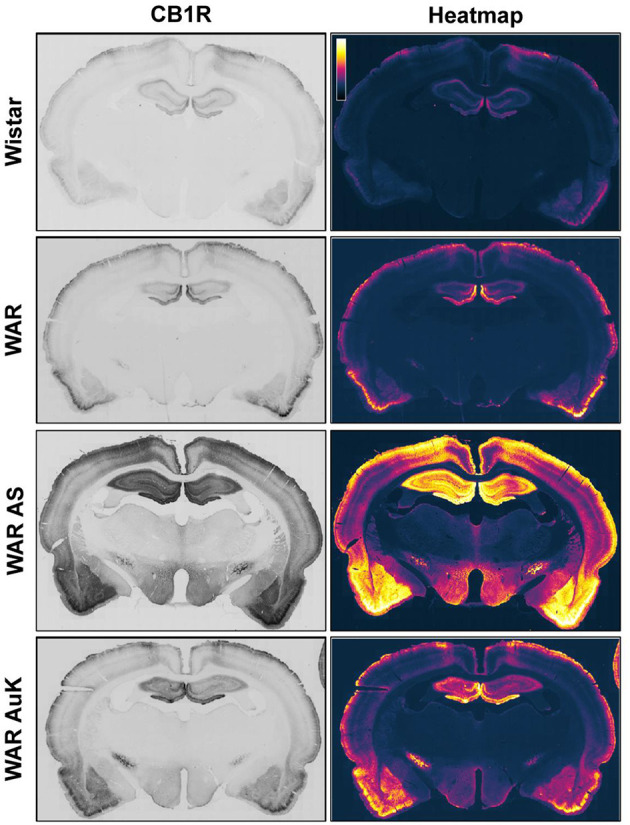

Changes in CB1R expression and functionality have already been detected in animal models of epileptic seizures and in humans with chronic seizures (Maglóczky et al., ref. 2010; Karlócai et al., ref. 2011; Rocha et al., ref. 2020). Goffin et al. (ref. 2011) assessed CB1R expression in tissue from humans with TLE and observed increased CB1R receptors expression in the seizure onset area, while CB1R expression was decreased in other areas, like the insular cortex, suggesting that different alterations in cannabinoid receptors expression could be associated with seizures expression and brain hyperexcitability (Goffin et al., ref. 2011). However, data of CB1R expression in audiogenic strains are scarce. Increased CB1R expression was observed in the inner molecular layer of WARs, when compared to control Wistars. Additionally, in WARs, acute and chronic AS increased CB1R expression in several hippocampal layers and in specific amygdala subnuclei, the basolateral, lateral, and basomedial nuclei. Acute AS also induced changes in CB1R in the central and medial amygdala nuclei. Moreover, it is worth to note that, changes in CB1R expression in lateral, basolateral, and basomedial amygdala nuclei were correlated with limbic seizure severity during the AuK (Lazarini-Lopes et al., ref. 2020a). See Figure 1 for a representative view of CB1R expression in limbic and cortical structures of audiogenic susceptible rats from the WAR strain.